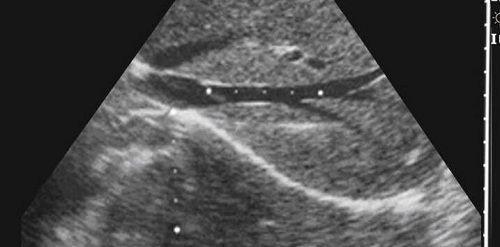

赵小姐在东京加藤医院做的B超检查图

于2016年,经历过前期的治疗后,开始东京加藤试管婴儿流程,考虑到赵小姐卵巢情况,东京加藤医生团队经过商榷后,决定采用了微刺激促排方案,促排流程并不怎么顺利,经历两个周期的促排才成功取卵;